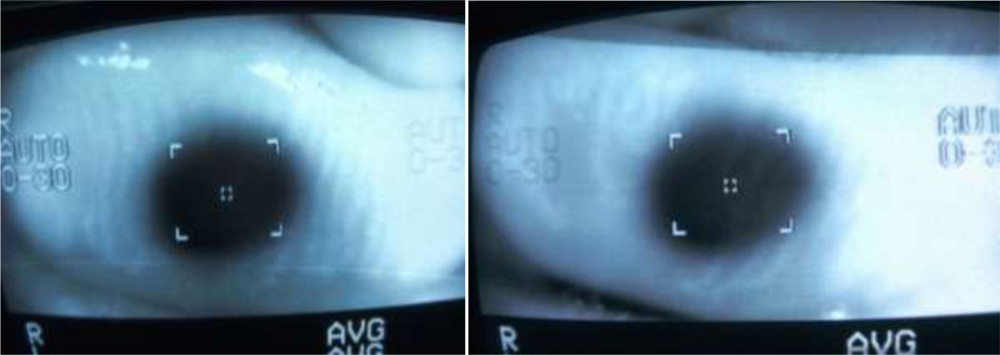

We tried to visualize the MGs by the infra red imaging using autorefractomer (Topcon RM8900), non contact tonometer (CT 80 Topcon), fundus camera (Zeiss), Zeiss  IOL master 500, specular miscroscope ( Topcon SP-3000p), ATLAS 9000 topographer and Visante AS-OCT which we have in our hospital. The images obtained were good enough to visualize the morphological features of MGs in these MGD eyes. We noted gland tortousity, shortening of the glands, broadening of the glands and gland drop-outs to various extent in many eyes. The images obtained by autorefractometer, IOL master, specular microscope, fundus camera, corneal topographer and Visante AS-OCT were better than those obtained by non-contact tonometer (NCT). The central shadowing of NCT while noting the MGs obscures the full visualization of MGs. The sample images obtained from these above mentioned instruments are as follows:

Non-contact tonometer:

Specular microscope